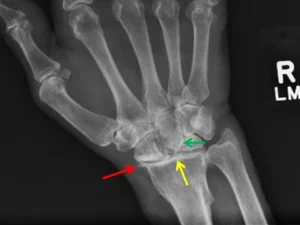

Radiografie van polsarthrose ten gevolge van niet geheelde breuk (links) of (onbehandeld) ligamentair letsel (rechts)

De diagnose van een polsarthrose wordt meestal zo op de raadpleging gesteld. Typisch is het uitvoeren van een RX aangewezen. Soms kan een CT of MRI nuttig zijn om de diagnose fijn te stellen.